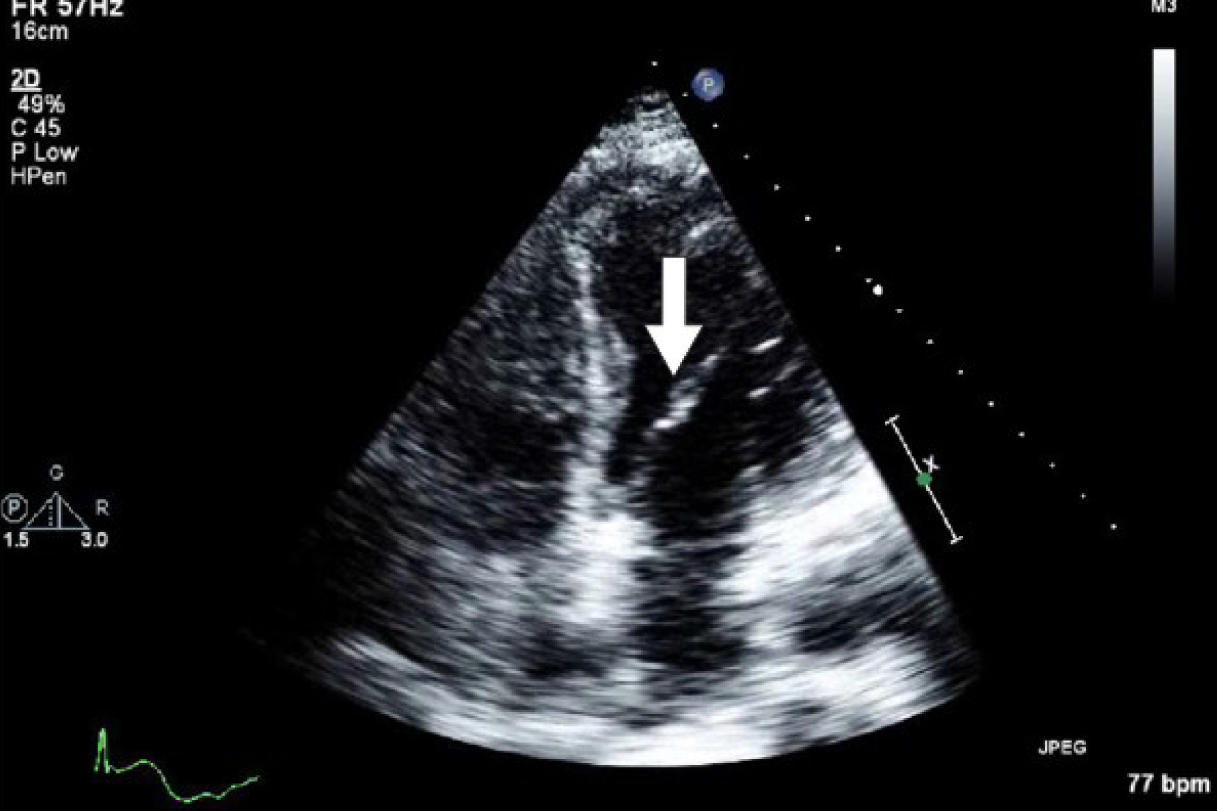

Initial laboratory studies were as follows: WBC 15.47 x 10/mcL, with a neutrophil count of 11.7 x 103/mcL; hemoglobin 13.3 gm/dL; platelet count 33 x 103/mcL; troponin 4.02 ng/mL; total CK 96 ng/mL, with a CK-MB 2.7 ng/mL and a relative index of 2.5; creatinine 0.8 mg/dL; international normalized ratio (INR) 1.56; PT 18.6 second; PTT 34.6 second; fibrinogen 209 mg/dL; fibrin degradation products (FDP) > 20 mcg/mL, and CA125 of 114 U/mL. Urinalysis showed moderate blood. Her EKG showed findings consistent with an acute, non-ST elevation myocardial infarction. CT imaging showed numerous large splenic, wedge-shaped hypodensities (Fig. 1) with similar areas in the kidneys bilaterally (Fig. 2), most consistent with infarcts. Also noted was a 12.4 x 8 x 11 cm right pelvic, complex, cystic and solid appearing mass (Fig. 3). An echocardiogram was obtained and showed mild mitral regurgitation and a moderate sized vegetation on the anterior mitral valve leaflet (Fig. 4). Lower extremity Duplex showed no apparent thrombosis.

![]() Click for large image | Figure 4. Echocardiogram showing mild mitral regurgitation and a moderate sized vegetation on the anterior mitral valve leaflet. |

We felt the patient had NBTE related to a pelvic malignancy. She was taken to the operating room for an exploratory laporotomy, total abdominal hysterectomy and bilateral salpingo-oophorectomy. A 12 cm right ovarian cystic mass was completely removed, and pathology confirmed a stage 1C clear cell adenocarcinoma with positive peritoneal fluid cytology. Following surgery, the patient demonstrated steady improvement in her hematologic laboratory studies with normalization of her platelet count and fibrinogen by day 5. She was started on anticoagulation therapy on the third day post-surgery and discharged on warfarin with the intention of completing a 6 months course. A one month follow up echocardiogram showed near complete resolution of the mitral vegetations.